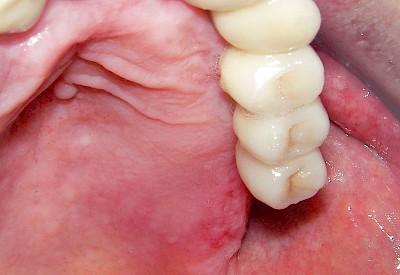

Aphte

Aphten lassen sich gut von Herpes unterscheiden, da Aphten in aller Regel nur einzeln und nicht Gruppiert auftreten. Die Ursachen sind bis heute nicht ganz geklärt. Unter anderem werden Viren aber auch Veranlagung diskutiert. Aphten sind vor allem nur an nicht-verhornten Schleimhautbereichen (Wange, Lippeninnenseite, Mundboden und Rachen) auf. In seltenen Fällen können die Blasen sehr groß sein oder doch in großer Zahl auftreten – hier sind Störungen des Immunsystems (Auto-Immunerkrankungen) häufig die Ursache.

Beispiele26 Bilder